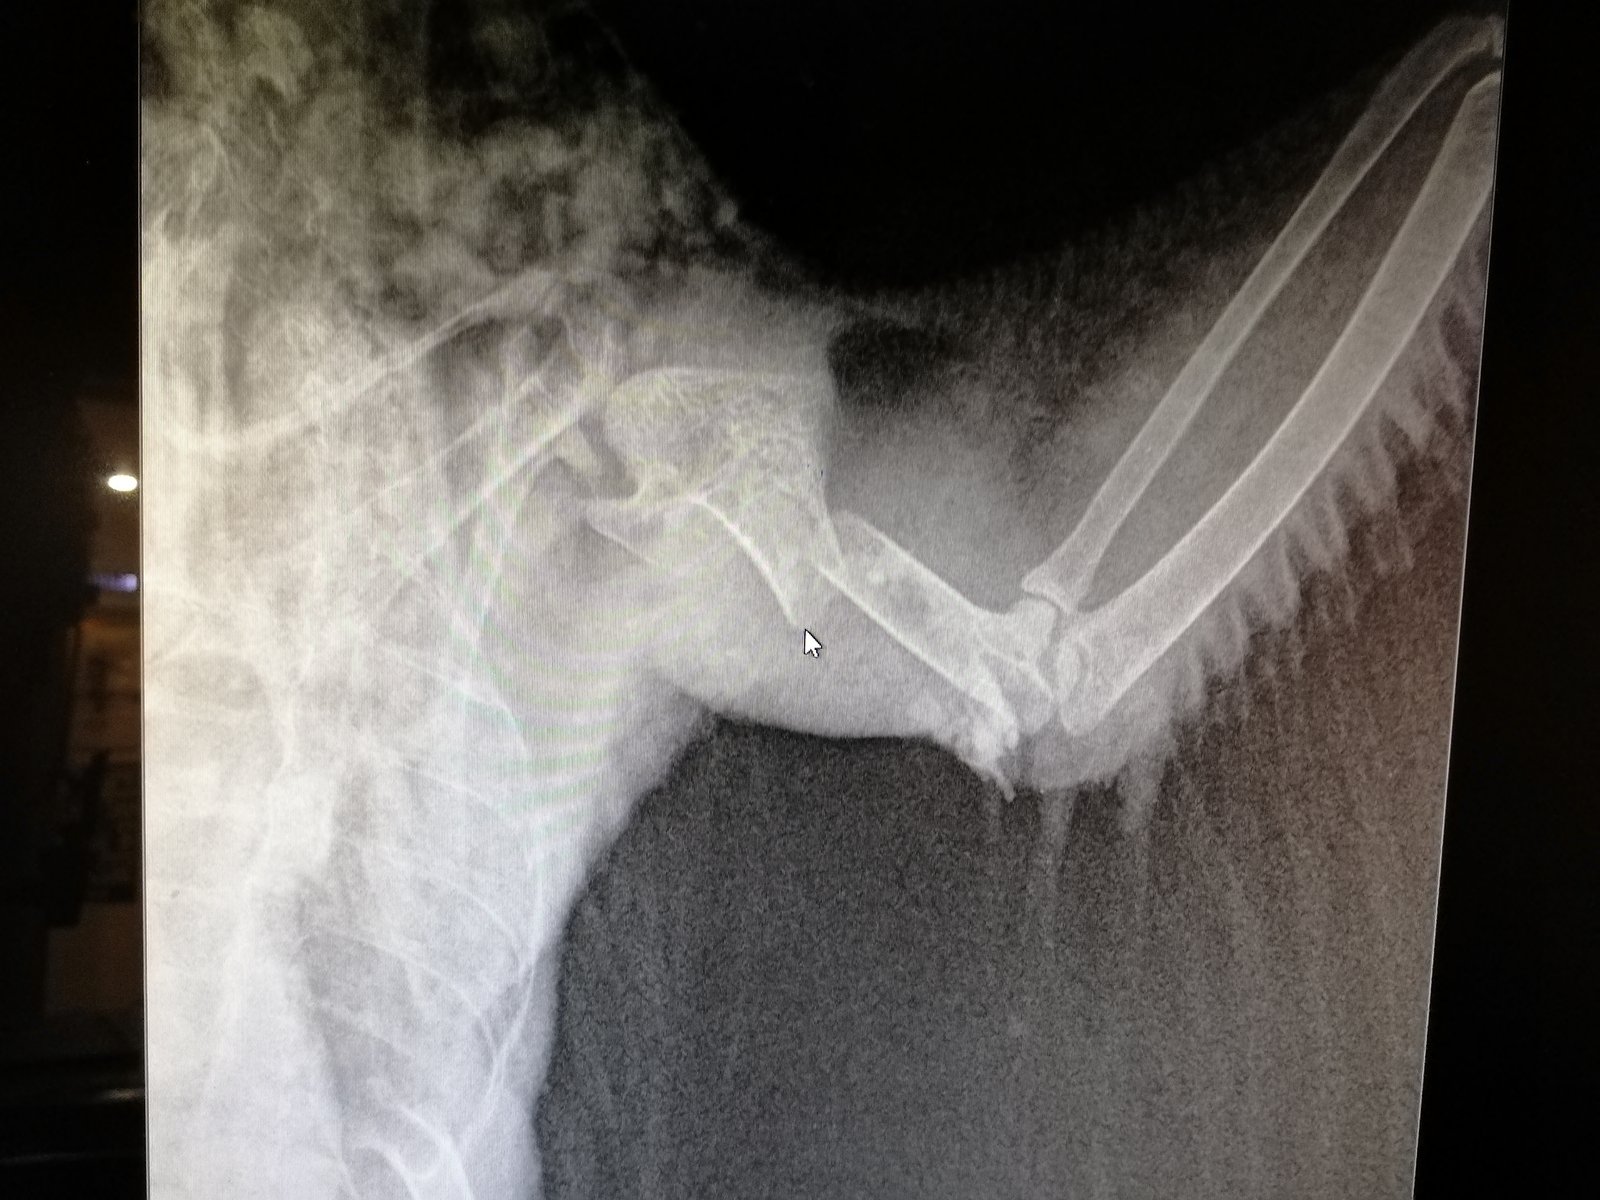

StanislavBird Опубликовано 12 сентября, 2021 Автор #13 Опубликовано 12 сентября, 2021 1 час назад, маленький принц сказал: там изнутри крыла рана? перелом закрытый или открытый? Перелом крыла открытый, но кость едва видно было. До рентгена вообще не видел, чтобы у него что-то торчало и кровоточило. Возможно, из-за самой процедуры рана открылась и было видно косточку. Сегодня рана не кровоточит. Сильнее расскрыть крыло не могу.

OFA Опубликовано 24 ноября, 2021 #40 Опубликовано 24 ноября, 2021 Объединила) @StanislavBird кости скорее всего уже давно схватились в таком положении, как на рентгене. Да, птиц останется нелетным, но операция по остеосинтезу это достаточно опасная процедура, т.к. не факт, что кости срастутся и не факт, что птиц хорошо перенесет наркоз. Если надумаете делать, то сначала рентген, консультация у врача, разбирающегося в птицах, а уж потом к хирургу на операцию